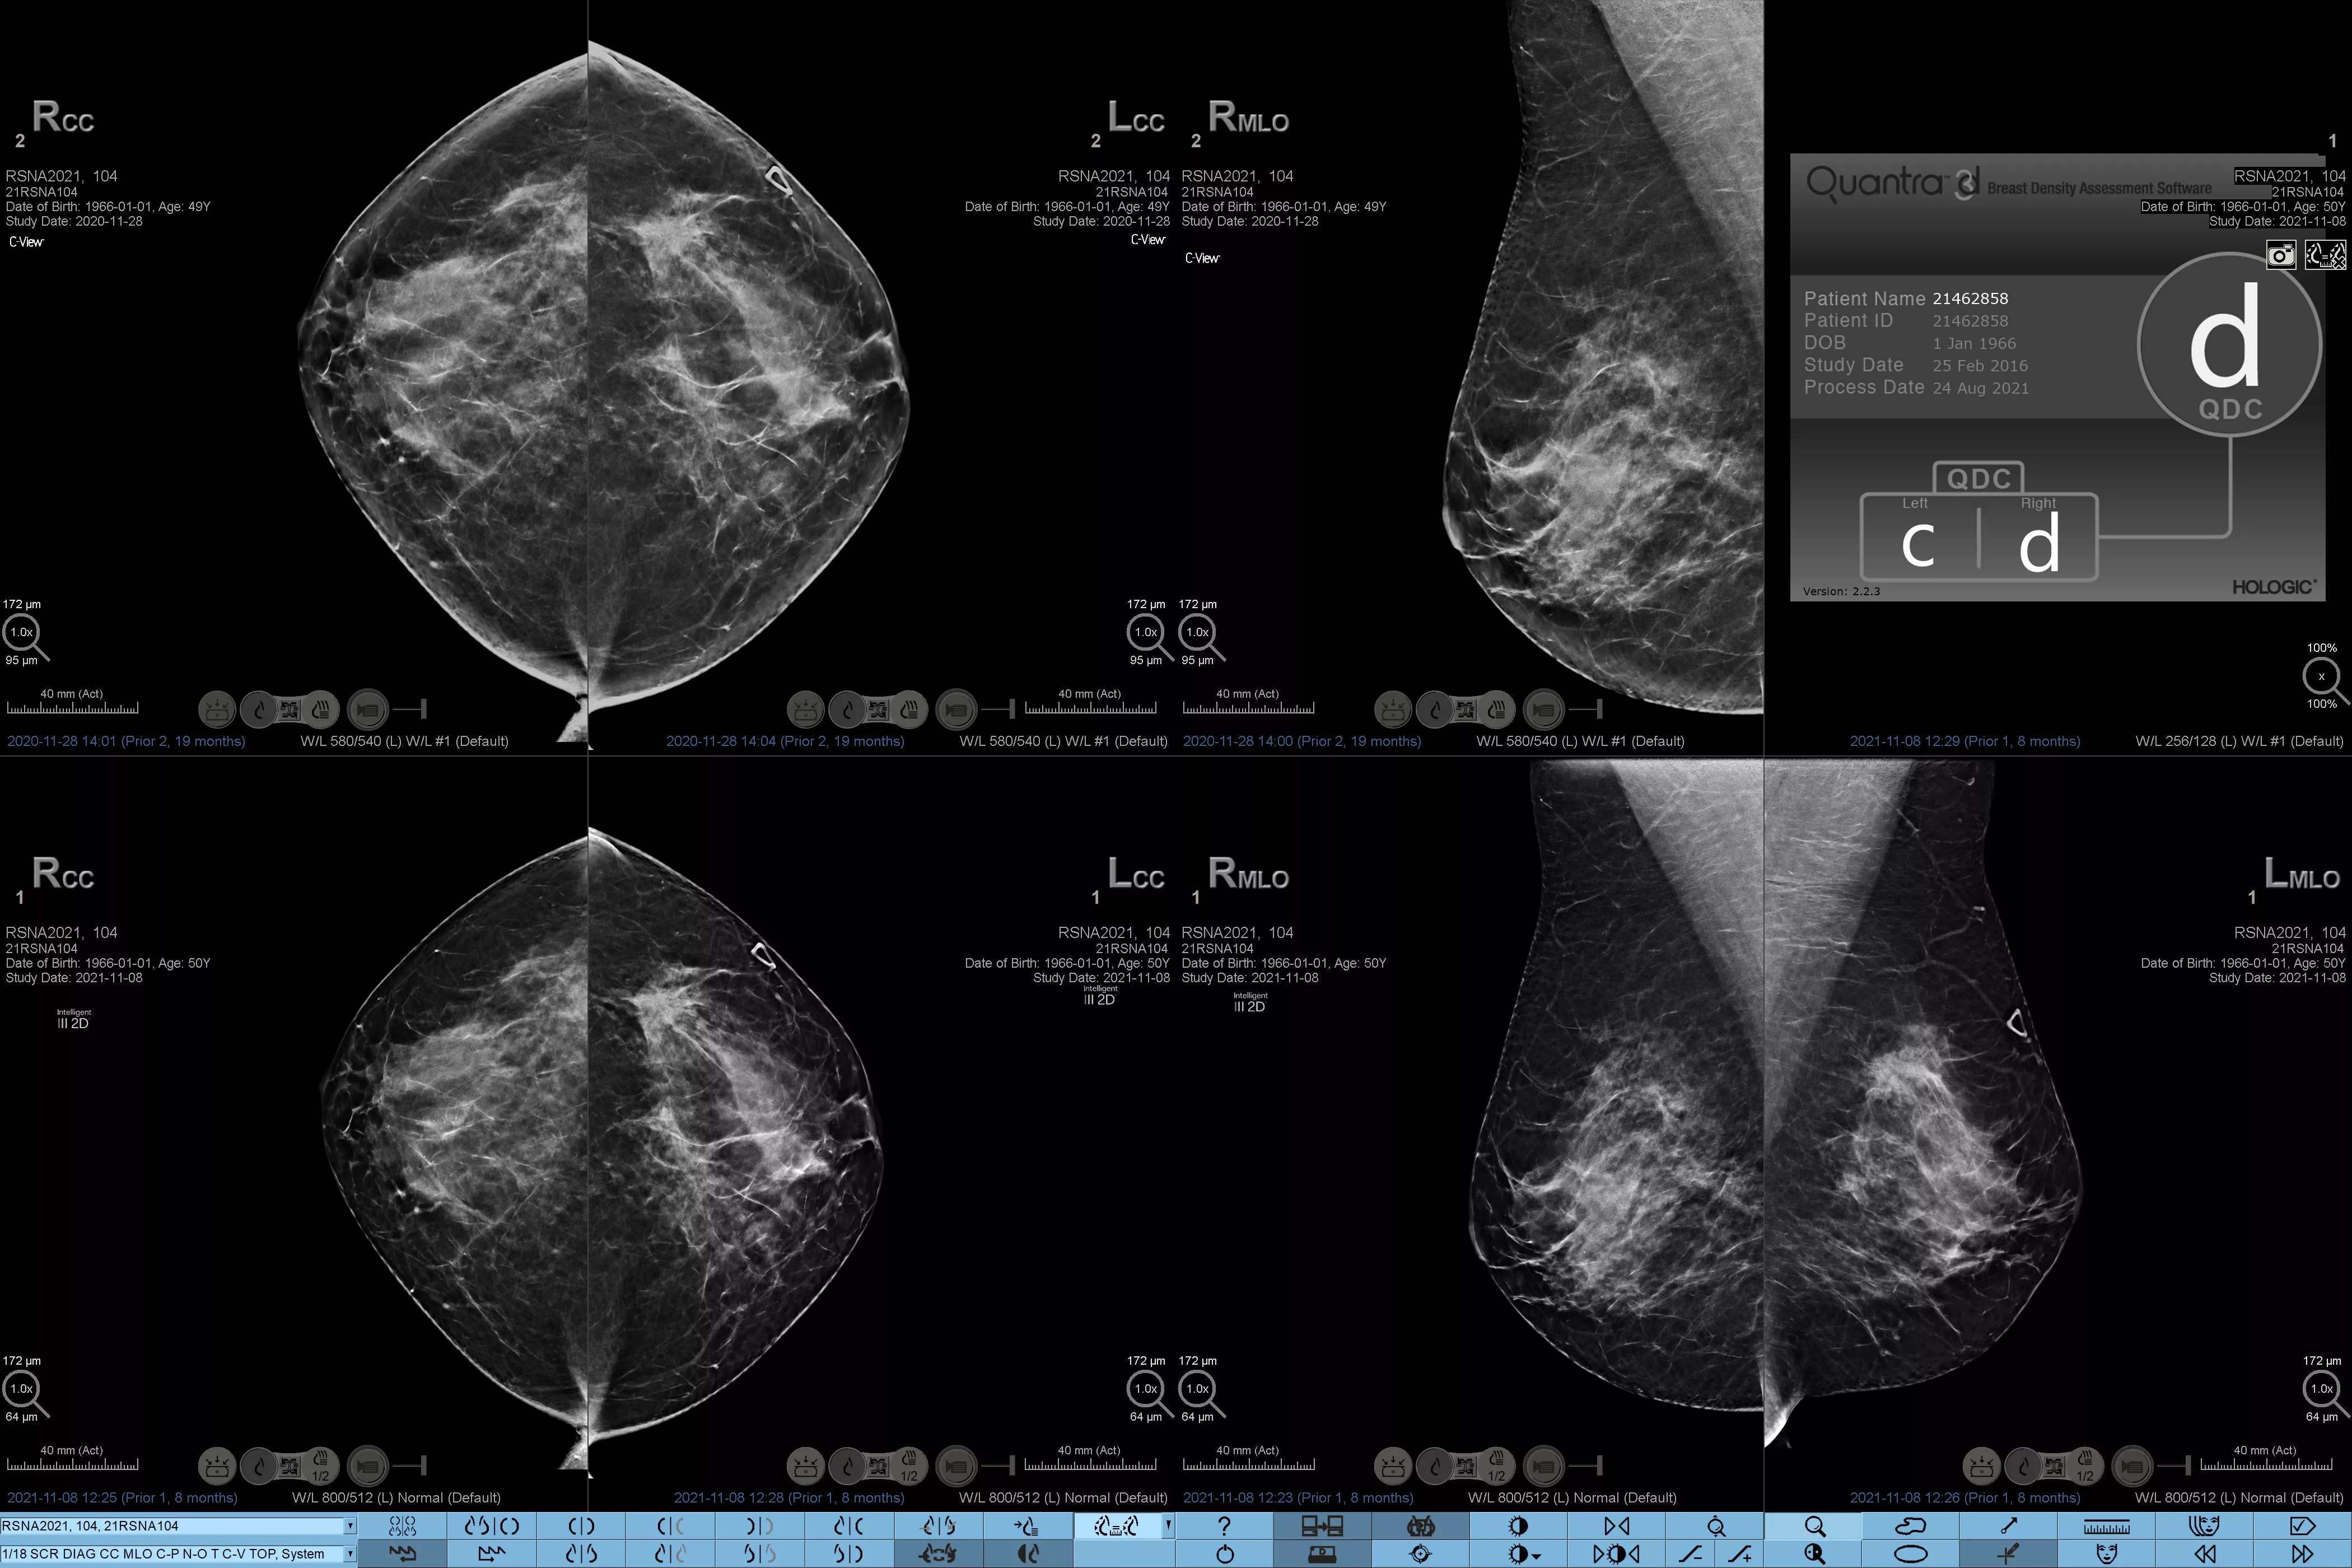

Higher breast density is known to increase a woman’s risk for breast cancer.1 The need for accurate, unbiased analysis is therefore critical. Powered by machine learning, Quantra technology software analyses both 2D™ and tomosynthesis images for distribution and texture of parenchymal tissue. It categorises breasts in four breast composition categories consistent with guidance from the American College of Radiology (ACR) BI-RADS Atlas 5th Edition.2

Objective machine learning algorithm that assigns breast density category based on analysis of breast tissue texture and patterns.

Standardisation

Standardise reporting across the radiology practice and provide a high standard of care.

• Overcoming subjectivity in visual assessment, providing more consistent, and more reliable scoring.*

• Elevating the standard of care and standardises reporting.